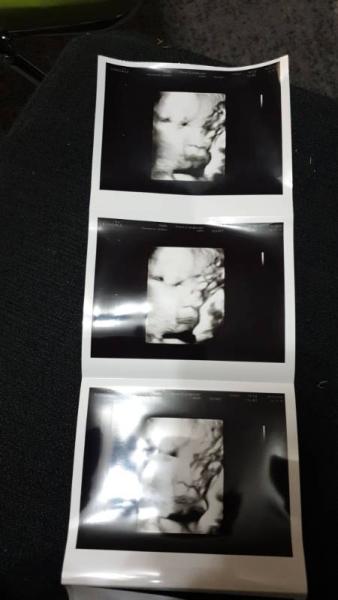

Hey Wow total süß Bei uns war es ähnlich er zeigte sich fast nie immer die Hände vor dem Gesicht. Beim letzten Termin konnten wir ihn endlich mal ansehen Wir kommen aus dem Februar Bus. LG

Bild zu